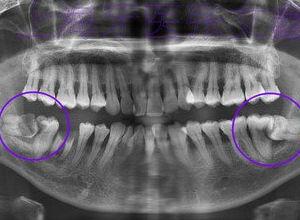

首先,我们来认识一下磨牙。磨牙分为两种:一种是清醒时的磨牙,另一种是睡眠时的磨牙。清醒时的磨牙可能是因为压力大、焦虑、紧张等原因引起的;而睡眠时的磨牙则可能与睡眠呼吸暂停、牙齿排列不齐等因素有关。

2. 生理因素:牙齿排列不齐、咬合不正、颞下颌关节疾病等生理因素也可能导致磨牙。